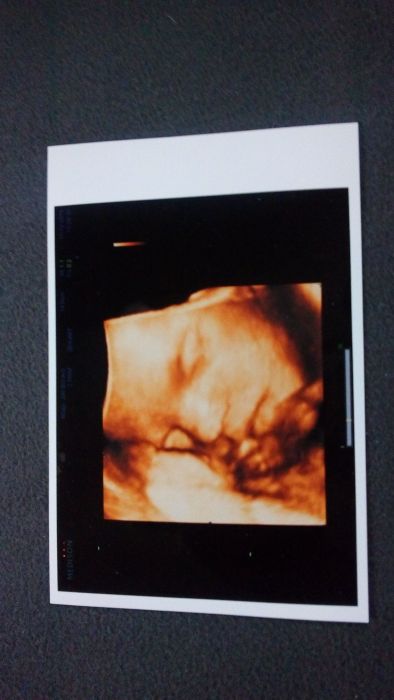

Ahoj holky, tak já jsem po kontrole dneska to byla rychlovlak nikdo tam nebyl ale doktor se jen kouknul na malou ale nic nemeril a nevazil říkal že mě čeká 7.1. Ten velký ultrazvuk že to probere všechno tam jen jsem zaslechla že placenta je vzadu(nvm či TK je dobře nebo ne?) a měla zrovna plný mocak a zpívala přidávám fotku (konečně první hezk fotka kde se nám ukázala)

Dawej, úžasná fotka!